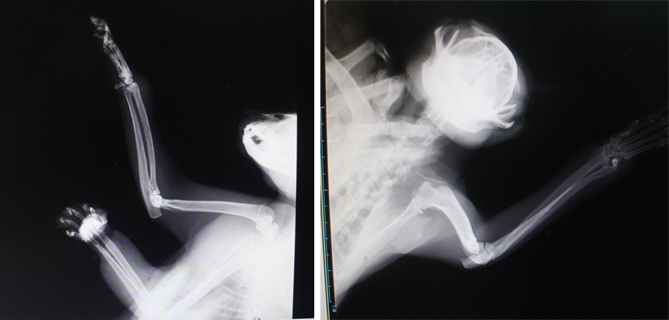

主題: 南寮收容所捕獸夾貓 申請者姓名: Star Wang 花色: 申請日期: 2014-09-09 21:58:14 申請者部落格: 申請者臉書網址: 所在縣市/合作醫院: 新竹市/新竺動物醫院 治療費用: 14000元 需求人數: 16人 已結案 (2014-11-12 11:46:14) 報名人員: 微光(已付款)、Yuii Chou(已付款)、君君(已付款)、Teresa Kao(已付款)、Sonya C(已付款)、Joba Huang(已付款)、Harn Cho(已付款)、cezeil(已付款)、Meng-Chen Tseng x2(已付款)、Janice(已付款)、sandroio(已付款)、Miguel from KJ(已付款)、饅頭阿姨(已付款)、姆姆 x2(已付款)、 候補人員: 動物病情說明: 南寮收容所救援出的捕獸夾貓,

左前臂已發黑,

發出腐爛惡臭,

且有蛆在傷口上爬………,

必須盡快安排進行截肢手術。

右前臂也有腫大處,

須拍攝x光片確認骨頭是否有傷。

血檢報告白血球五萬多。

8/19完成左前臂截肢手術,

右前臂x光片確認骨頭無傷,多處化膿,應是欲掙脫捕獸夾時弄傷自己。